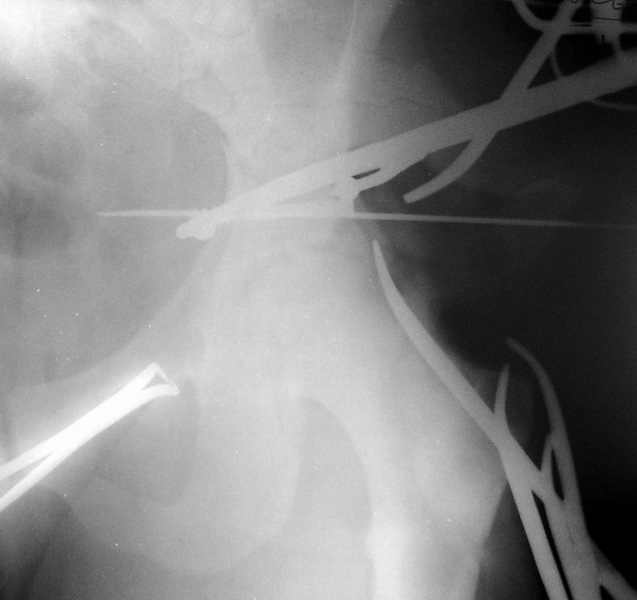

Тяжелая политравма у юноши С. 20 лет - 23.02.20030г. - падение с высоты 8 этажа. В настоящее время состояние стабилизировалось, возможен остеосинтез. Аппарат наложен при поступлении. Д-З: Политравма Перелом С2 б/смещения Перелом левого бедра(см.снимок),правой голени (стабилизирован),обеих пяточных костей со смещением,таза (см.снимок) Нужно ли произвести синтез таза? или ограничиться синтезом бедра? каким??

Оговорюсь сразу, что DHS или DCS не имею, состояние больного позволяет произвести и синтез таза, но надо ли это, учитывая множественность переломов др.локализации? Извиняюсь, что нет др. снимков и за качество, сканер с незким разрешением. Благодарю за советы !

Пока видно, что имеется тяжелый оскольчатый перелом вертлужной впадины, который надо открыто синтезировать. Для уточнения диагноза необходимо сделать косые проекции (Judet views). Не помешала бы КТ.

При таком переломе бедра в нашей клинике был бы выполнен закрытый интрамедуллярный остеосинтез с блокированием. Лечили раньше подобные вещи и в аппарате. Если делать пластиной, лучше по принципам "биологического остеосинтеза", т.е. за идеальной репозицией не гнаться, промежуточные отломки не скелетировать.

В качестве альтернативны интрамедуллярному штифтиванию можно фиксировать 95 градусной blade plate.

Применяемая в настоящее время миниинвазивная техника фиксации позволяет из двух кожных разрезов -один в области большого вертела (место введения клинка) другой на уровне дистального фрагмента позволяет нетравматично и стабильно фиксировать перелом. Для блокирующего гвоздя - проксимальный отломок слишком короткий, поэтому могут возникнуть трудности с проксимальным

блоком гвоздя.

Для уточнения диагноза необходим обзорный снимок таза и Judet проекции. Судя по присланной короткой рентгенограмме, один из компонентов перелома - отрыв свода, точно имеется ступенеобразная деформация нагружаемой поверхности и без открытой репозиции ничего хорошего не будет. Если в ближайшую неделю восстановительная опеперация не будет сделана, то лучше потом и не пытаться, а ждать сращения бедра для эндопротеза.

Мы бы без колебаний оперировали для восстановления конгруентности.